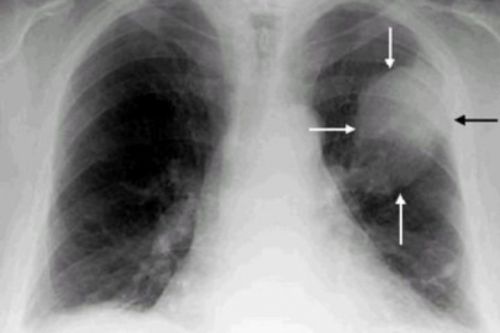

Пневмония на рентгене

Если вы ощущаете неприятные ощущения в грудной клетке, тяжесть в легких слева, то могут быть проблемы с легкими, а именно пневмония или плеврит.

Дополнительными симптомами заболевания считаются головная боль, снижение физической активности и слабость. Выявить пневмонию можно только после рентгенографии и цитологического анализа.

3. При плеврите и воспалении легких

Если начинают болеть легкие в области спины, необходимо исключить заболевания легочной системы. Характерно, что боль при развитии пневмонии вызвана исключительно присоединением миозитов или плевритов.

При этом, помимо болевого симптома, наблюдаются следующие признаки:

- стойкая гипертермия;

- повышенная усталость и общее ослабление организма;

- покалывания в спине при дыхании, особенно при глубоком вдохе;

- возможна одышка и сильный кашель.

Пальпаторно (прощупыванием) выявляется локальная болезненность в области спины, при аускультации (прослушивании) слышны крепитация (легкое потрескивание, хруст), а также шумы, напоминающие трение. Плевральные боли нередко сопровождают развитие туберкулеза. При этом боль локализуется в верхней части легких, а в области спины отмечается боль в области трапециевидной мышцы.

Диагностика заключается в проведении рентгенографии, а при туберкулезе выполняется ряд специальных проб на определение специфического возбудителя. Лечебные мероприятия при заболеваниях легких заключаются, прежде всего, в антибиотикотерапии (Ампициллин, Цефазолин, Оксациллин и т.д.), а также противокашлевых средств и препаратов для разжижения и выведения мокроты из легких (Либексин, Бромгексин, Амбробене и т.д.).